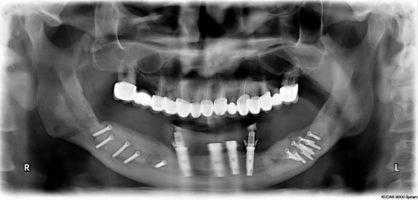

Дентальная имплантация пациент А. через 6 месяцев

Ортопантомограмма пациента А. после дентальной имплантации

Ортопантомограмма пациента Б. после операции

Расщепленные свободные костные трансплантаты с ветвей нижней челюсти были зафиксированы с вестибулярной и язычной сторон, пространство между трансплантатами аугментировано ксеногенным материалом «БиОсс». Раны ушиты П-образными и узловыми швами с формированием слизисто-мышечных «мешочков».

С 2010 г. по 2011 г. в отделении пластической и челюстно-лицевой хирургии РНЦХ им. акад. Б.В. Петровского выполнено 15 операций на верхней челюсти с использованием гребня подвздошной кости и 20 операций на нижней челюсти с теменными аутотрансплантатами. Во всех клинических ситуациях была достигнута возможность постановки дентальных имплантатов.

Разработанный метод трехмерной вертикальной реконструкции нижней челюсти теменными трансплантатами позволяет увеличить высоту челюсти в боковых отделах до 10-15 мм, ширину до 10-13 мм по нашей практике. Особенностью и новизной данной операции является фиксация костного трансплантата с язычной стороны.